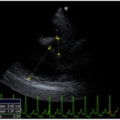

症例1:【マルチーズ 12歳齢 去勢オス】

C:超音波 僧帽弁逆流、三尖弁逆流、大動脈弁逆流の動画

胸部レントゲン検査において重度の心拡大と肺水腫が認められた。超音波検査では、重度の僧帽弁閉鎖不全症、三尖弁閉鎖不全症、中程度の大動脈弁閉鎖不全症を合併していることが判明した。三尖弁逆流速度から肺高血圧症が示唆された。